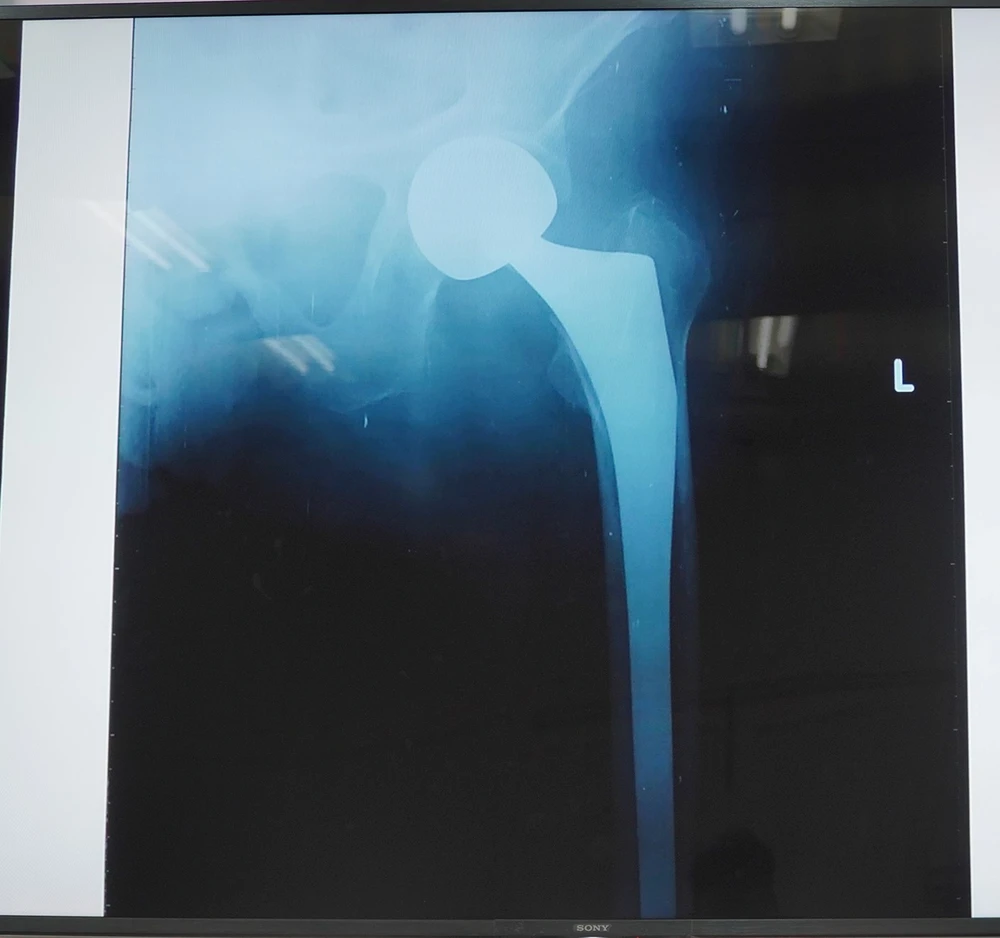

Hình ảnh khớp háng nhân tạo được thay cho cụ bà 106 tuổi. Ảnh: BVCC

Ngày 14-1, các bác sĩ Khoa Chấn thương chỉnh hình Bệnh viện (BV) Chợ Rẫy (TP.HCM) cho biết vừa phẫu thuật thay khớp háng nhân tạo cho cụ bà NTK (106 tuổi) bị gãy cổ xương đùi chân bên trái.

Đây là trường hợp lớn tuổi nhất được phẫu thuật thay khớp háng tại BV Chợ Rẫy.